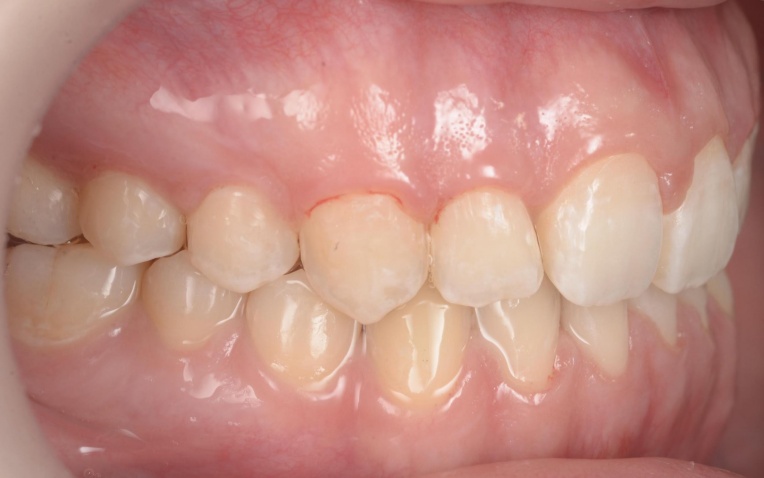

「前歯が噛み合わないので治したい」とご相談いただきました。 |

拝見したところ、重度の開咬(かいこう)が認められました。 |

見た目と噛む機能の両方を改善するため、矯正治療を提案し、同意いただきました。 |

18ヶ月 |